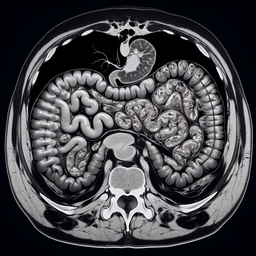

МРТ шлунка

Магнітно-резонансна томографія (МРТ) шлунка – це високоточний метод діагностики, який дозволяє отримати детальну інформацію про структуру шлунка та оточуючих його тканин. Ось основні етапи проходження МРТ шлунка в приватній клініці: